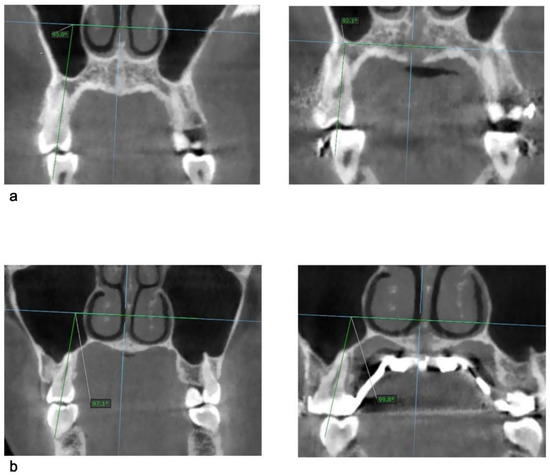

- Paredes, N.; Colak, O.; Sfogliano, L.; Elkenawy, I.; Fijany, L.; Fraser, A.; Zhang, B.; Moon, W. Differential assessment of skeletal, alveolar, and dental components induced by microimplant-supported midfacial skeletal expander [MSE], utilizing novel angular measurements from the fulcrum. Prog. Orthod. 2020, 21, 18. [Google Scholar] [CrossRef] [PubMed]

- Colak, O.; Paredes, N.A.; Elkenawy, I.; Torres, M.; Bui, J.; Jahangiri, S.; Moon, W. Tomographic assessment of palatal suture opening pattern and pterygopalatine suture disarticulation in the axial plane after midfacial skeletal expansion. Prog. Orthod. 2020, 21, 1–9. [Google Scholar] [CrossRef]